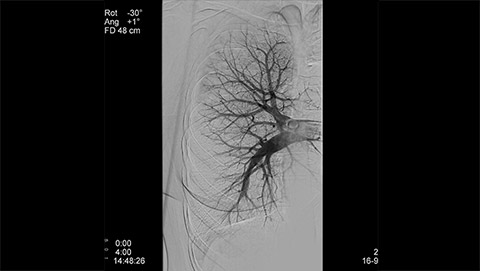

Dynamic 3D Roadmap provides a sustainable 3D roadmap to support interventional procedures. Dynamic 3D Roadmap matches the real-time 2D fluoroscopy images with the 3D-RA reconstruction of the vessel tree. It provides a 3D real-time insight of the advancement of the guide wire, catheter and coils through complex vessel structures. The Unsubtracted 3D Roadmap option reduces subtraction artifacts caused by patient breathing and movements, providing a clear roadmap during abdominal and thoracic interventions.

Live 3D Roadmap allows you to follow the advancement of guidewires, catheters and coils in real-time. It automatically adapts in real-time to changes in C-arm angulation and rotation, table movement, field of view and source-image distance.